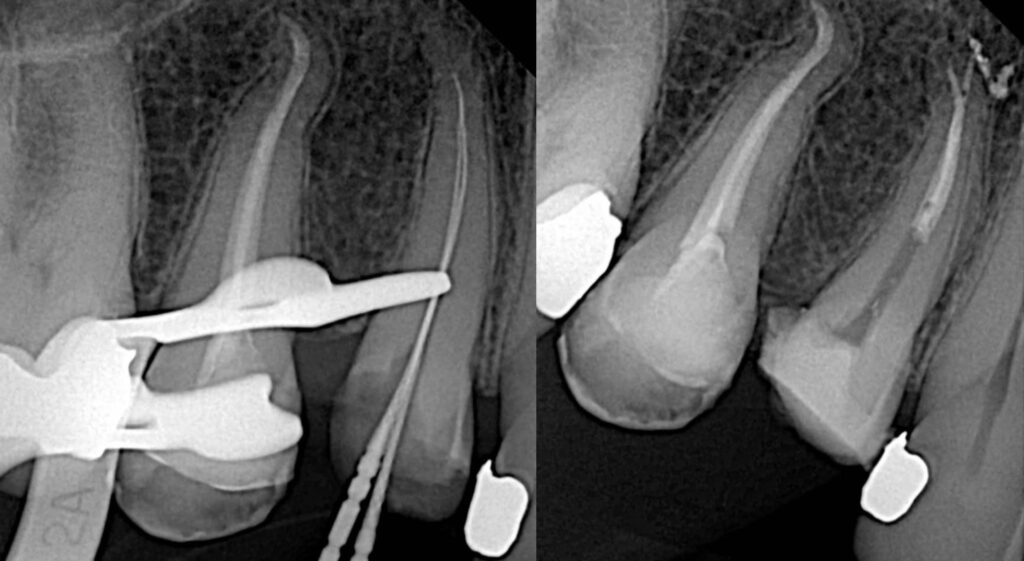

Initial manual preparation was completed up to size 20. Final canal shaping was performed using the Rogin Super Flexi Files Kit to size 25/0.04. These files, made from heat-treated Nickel-Titanium CM wire, provided excellent flexibility for safe navigation of the canal curvature, while the square cross-section ensured effective cutting and debris removal with minimal transportation.

Irrigation was carried out using 5.25% sodium hypochlorite, followed by saline and 17% EDTA. Sodium hypochlorite was activated ultrasonically to enhance debridement efficacy. The canals were then obturated using the warm vertical compaction technique, achieving a dense and three-dimensional fill.

Rogin Super Flexi Files demonstrated exceptional performance in this case, offering both flexibility and efficiency in shaping narrow, curved canals. Their non-cutting tip ensured safety, minimizing the risk of lateral perforation. Over the course of more than 20 complex cases, the Rogin file system has proven to be reliable and effective for clinical use.